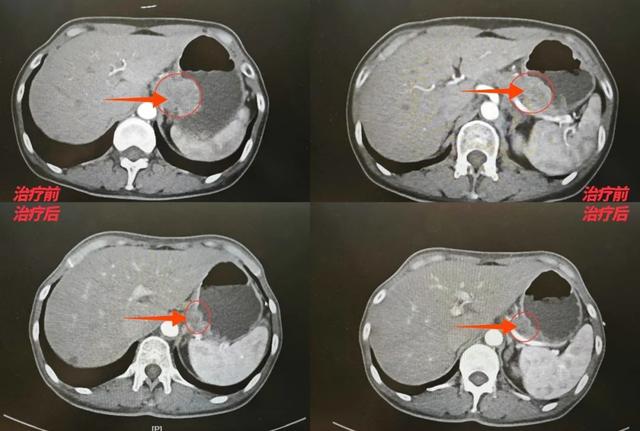

治疗初期,王女士经历了恶心、乏力等副作用,但在肿瘤(胃肠)外科医护团队的全程监护和家人的支持下,她坚持完成了四个周期的化疗。影像复查显示:胃部肿瘤明显缩小,与周围组织的粘连显著改善。